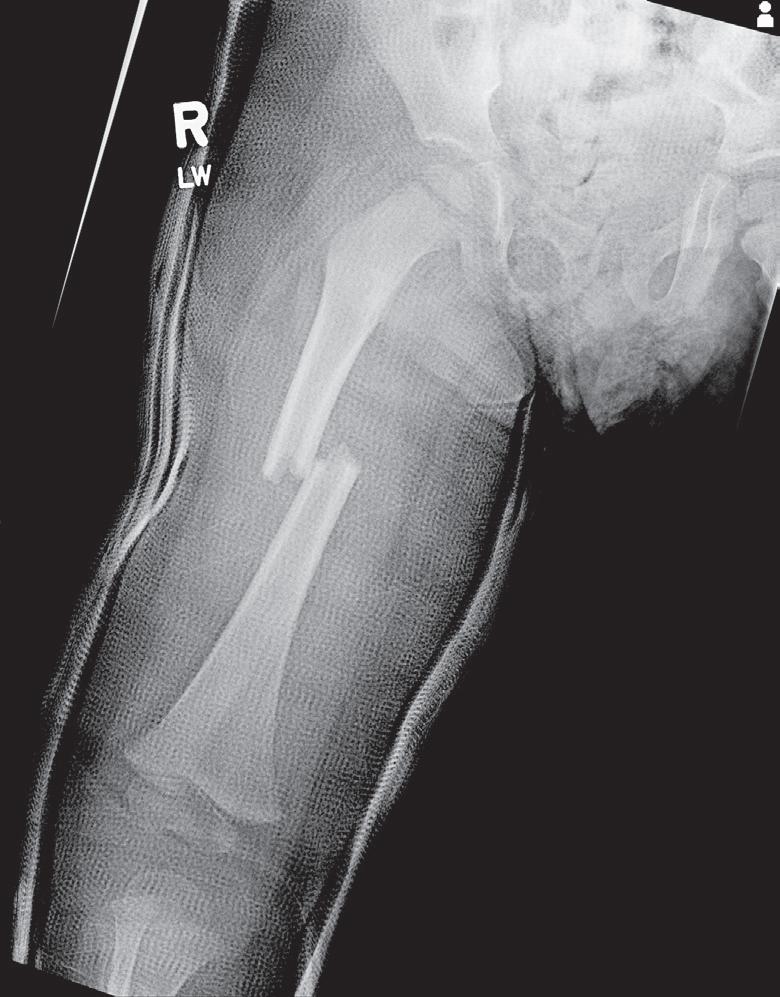

Children also vary from adults as bone overgrowth has been seen in pediatric fracture healing. Fractures distant from the physis can also result in changes in growth patterns. This is particularly evident in overgrowth after femoral shaft

fractures; some investigators have hypothesized that disruption of the periosteal sleeve or increasing vascularity of the bone after a fracture increases longitudinal growth.19,23 This phenomenon most frequently compensates for fractures that heal with shortening but occasionally results in the injured limb being longer. The same cells and processes that govern normal growth are involved in fracture healing.55 Studying growth mechanisms with microarray technology demonstrates the complexity of the genetic response to a fracture. In a study of femoral overgrowth mechanisms in a rat model, more than 5000 genes in the proximal femoral physis were noted to respond significantly to fractures. Genes related to vascular development and growth were downregulated, which casts doubt on the widely held assertion that femoral overgrowth is a consequence of increased vascularity in the limb after a fracture.35 It has been postulated that mechanical factors, such as tension within the surrounding periosteum, may have some control over the growth rate.18,19 This is clinically best exemplified by posttraumatic tibia valgus after proximal tibial metaphyseal fractures in children (the Cozen phenomenon).56–58 Recent basic science data by Halanski et al59 confirmed that disruption of the periosteum would accelerate growth. This pattern of overgrowth is not observed in adult fracture healing, and thus, fracture shortening at union will be permanent.

Fig. 1.3 Anteroposterior (A) and lateral (B) radiographs of the knee of a 12-year-old child 6 months after a femoral shaft fracture. Arrest lines parallel to the physis can be seen in the metaphyseal area of the distal end of the femur and proximal tibia (arrows). The temporary depression of growth at the time of injury results in more horizontal trabeculae being laid down, thereby increasing the density of bone at that level.